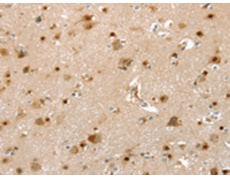

ELISA, IHC |

IHC positive control: |

Human brain and Human tonsil |

IHC Recommend dilution: |

25-100 |